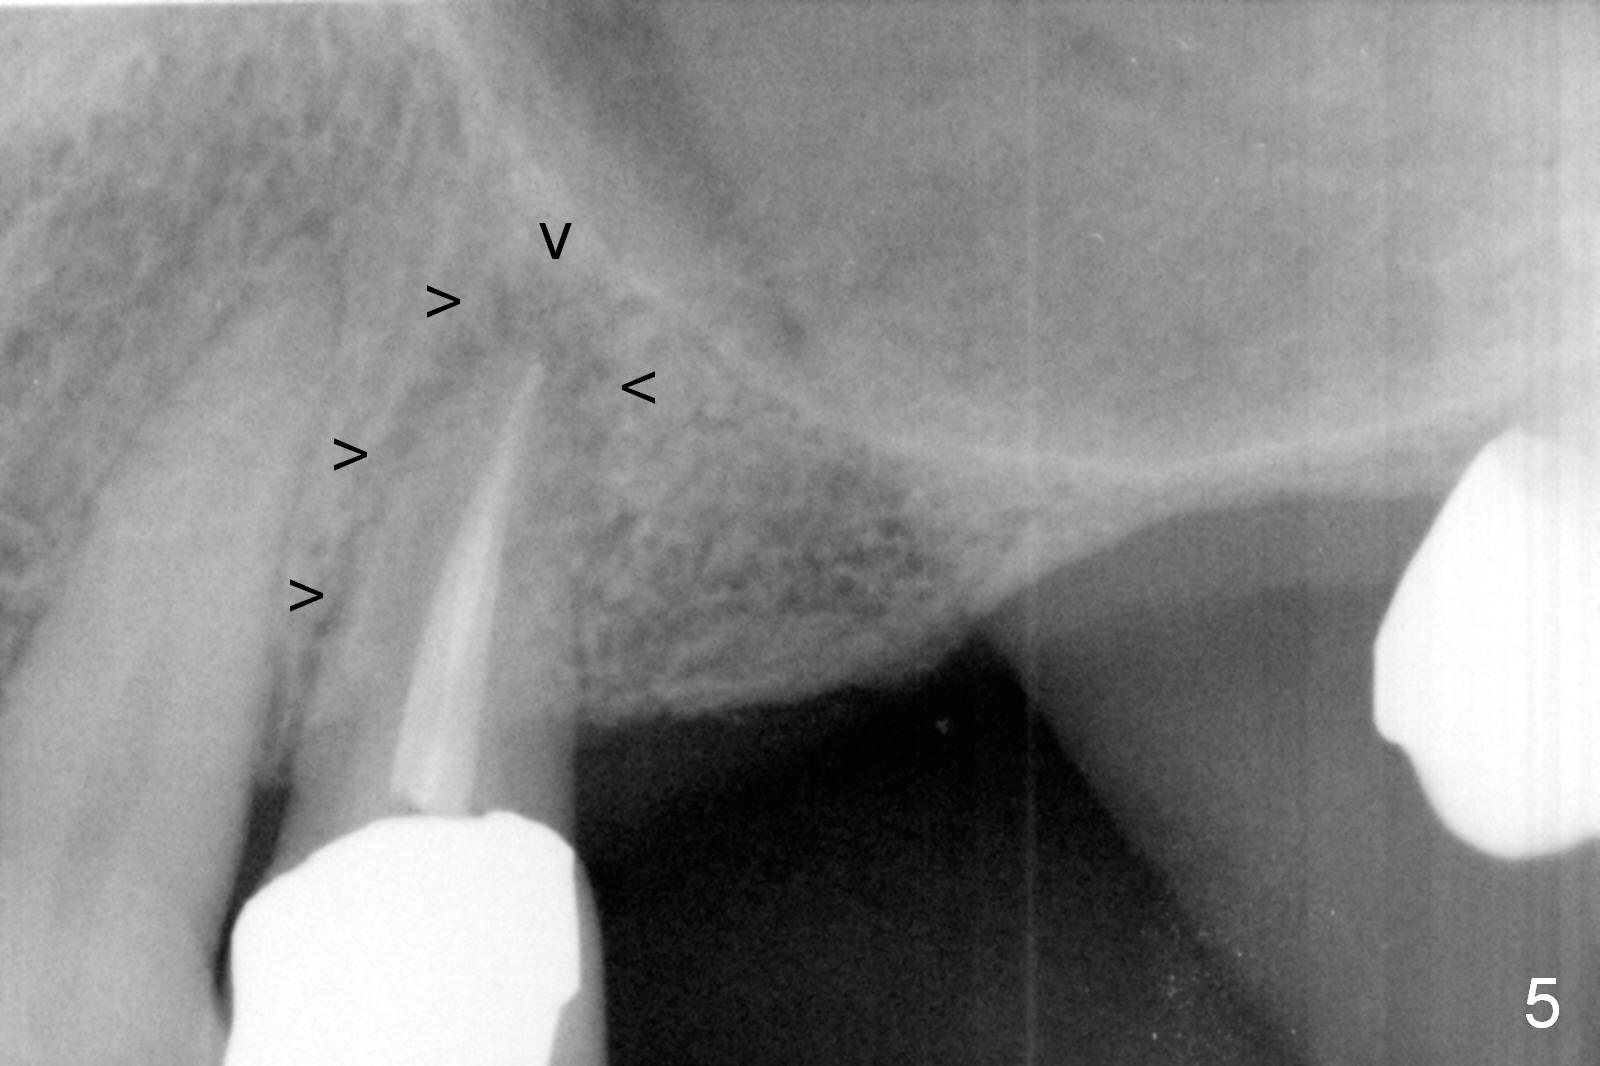

A 64-year-old man (MM) had caries at the tooth #12 (Fig.1), requiring root canal therapy (RCT, Fig.2). One year later, the periapical radiolucency reduces (Fig.3 <, as compared to that in Fig.2). The tooth remains asymptomatic 7 years posts RCT (Fig.4). A year later, the tooth has pain and buccal gingival swelling (probing tenderness); periradicular radiolucency is evident (Fig.5 arrowheads). It appears that the root fractures. Between the 7th and 8th years post RCT, the patient masticated mainly on the left side, while implants were placed at #30 and 31. The patient plans to have 4 implants in the upper left sextant (Fig.6). While implants are being placed at the site of #12 (Clindamycin) and 13, sinus lift seems mandatory at the sites of #13 and (initial depth will be 5-6 mm). By the time implants to be placed at #14 and #15, the bone height may increase.